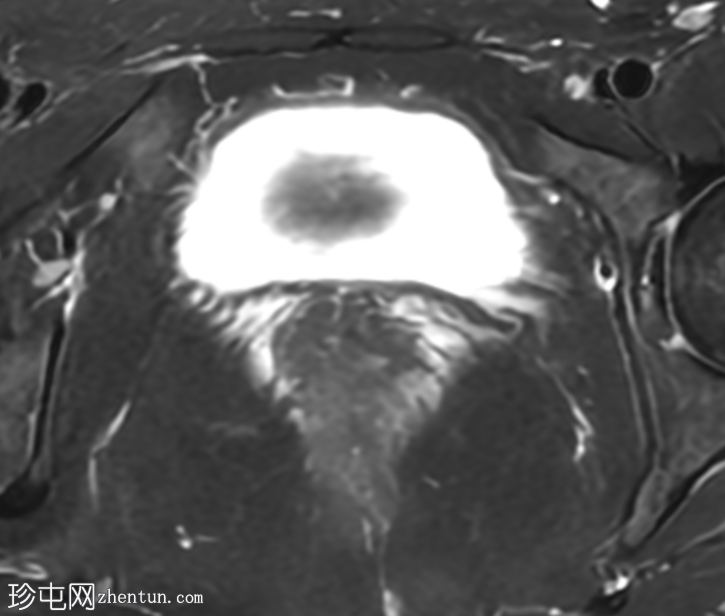

轴位T1加权像

增强脂肪抑制像

盆腔MRI显示右侧卵巢解剖位置可见一边界清晰的卵圆形肿块。该病灶由囊性和实性成分组成。囊性部分壁薄,在T2加权像上呈均匀高信号,在T1加权脂肪抑制序列上呈低信号,无对比剂增强。该实性成分的信号特征与正常卵巢组织相似,DWI成像未见扩散受限,静脉注射造影剂后未见异常强化。

本例中,盆腔MRI显示,患者右侧卵巢解剖位置存在一个边界清晰的附件肿块,该患者有20年前行双侧输卵管卵巢切除术的病史。该病灶包含囊性和实性成分,其中实性部分表现出与正常卵巢组织相似的信号特征。无扩散受限和无可疑的增强扫描强化提示排除恶性病变。这些影像学特征结合相关的手术史进行解读,符合残留卵巢组织的特征,支持卵巢残留综合征的诊断。此外,还发现对侧子宫左侧延伸出一个管状薄壁囊性结构,末端呈盲端。其形态、信号特征和无强化表现符合输卵管残端或输卵管残端积水,这是输卵管切除术后常见的术后表现。附件残余的存在进一步支持术后病因,而非原发性妇科肿瘤

主要鉴别诊断包括腹膜包涵囊肿、子宫内膜异位症相关囊肿和附件肿瘤。腹膜包涵囊肿通常位于腹膜腔内,不含类似卵巢组织的实性成分。子宫内膜异位囊肿通常在T1加权像上表现为高信号,T2加权像上出现阴影,并具有其他特征性MRI表现,而本例4中均未见这些表现。鉴于无扩散受限、无可疑强化以及实性成分的良性影像学表现,肿瘤性病变的可能性较小。